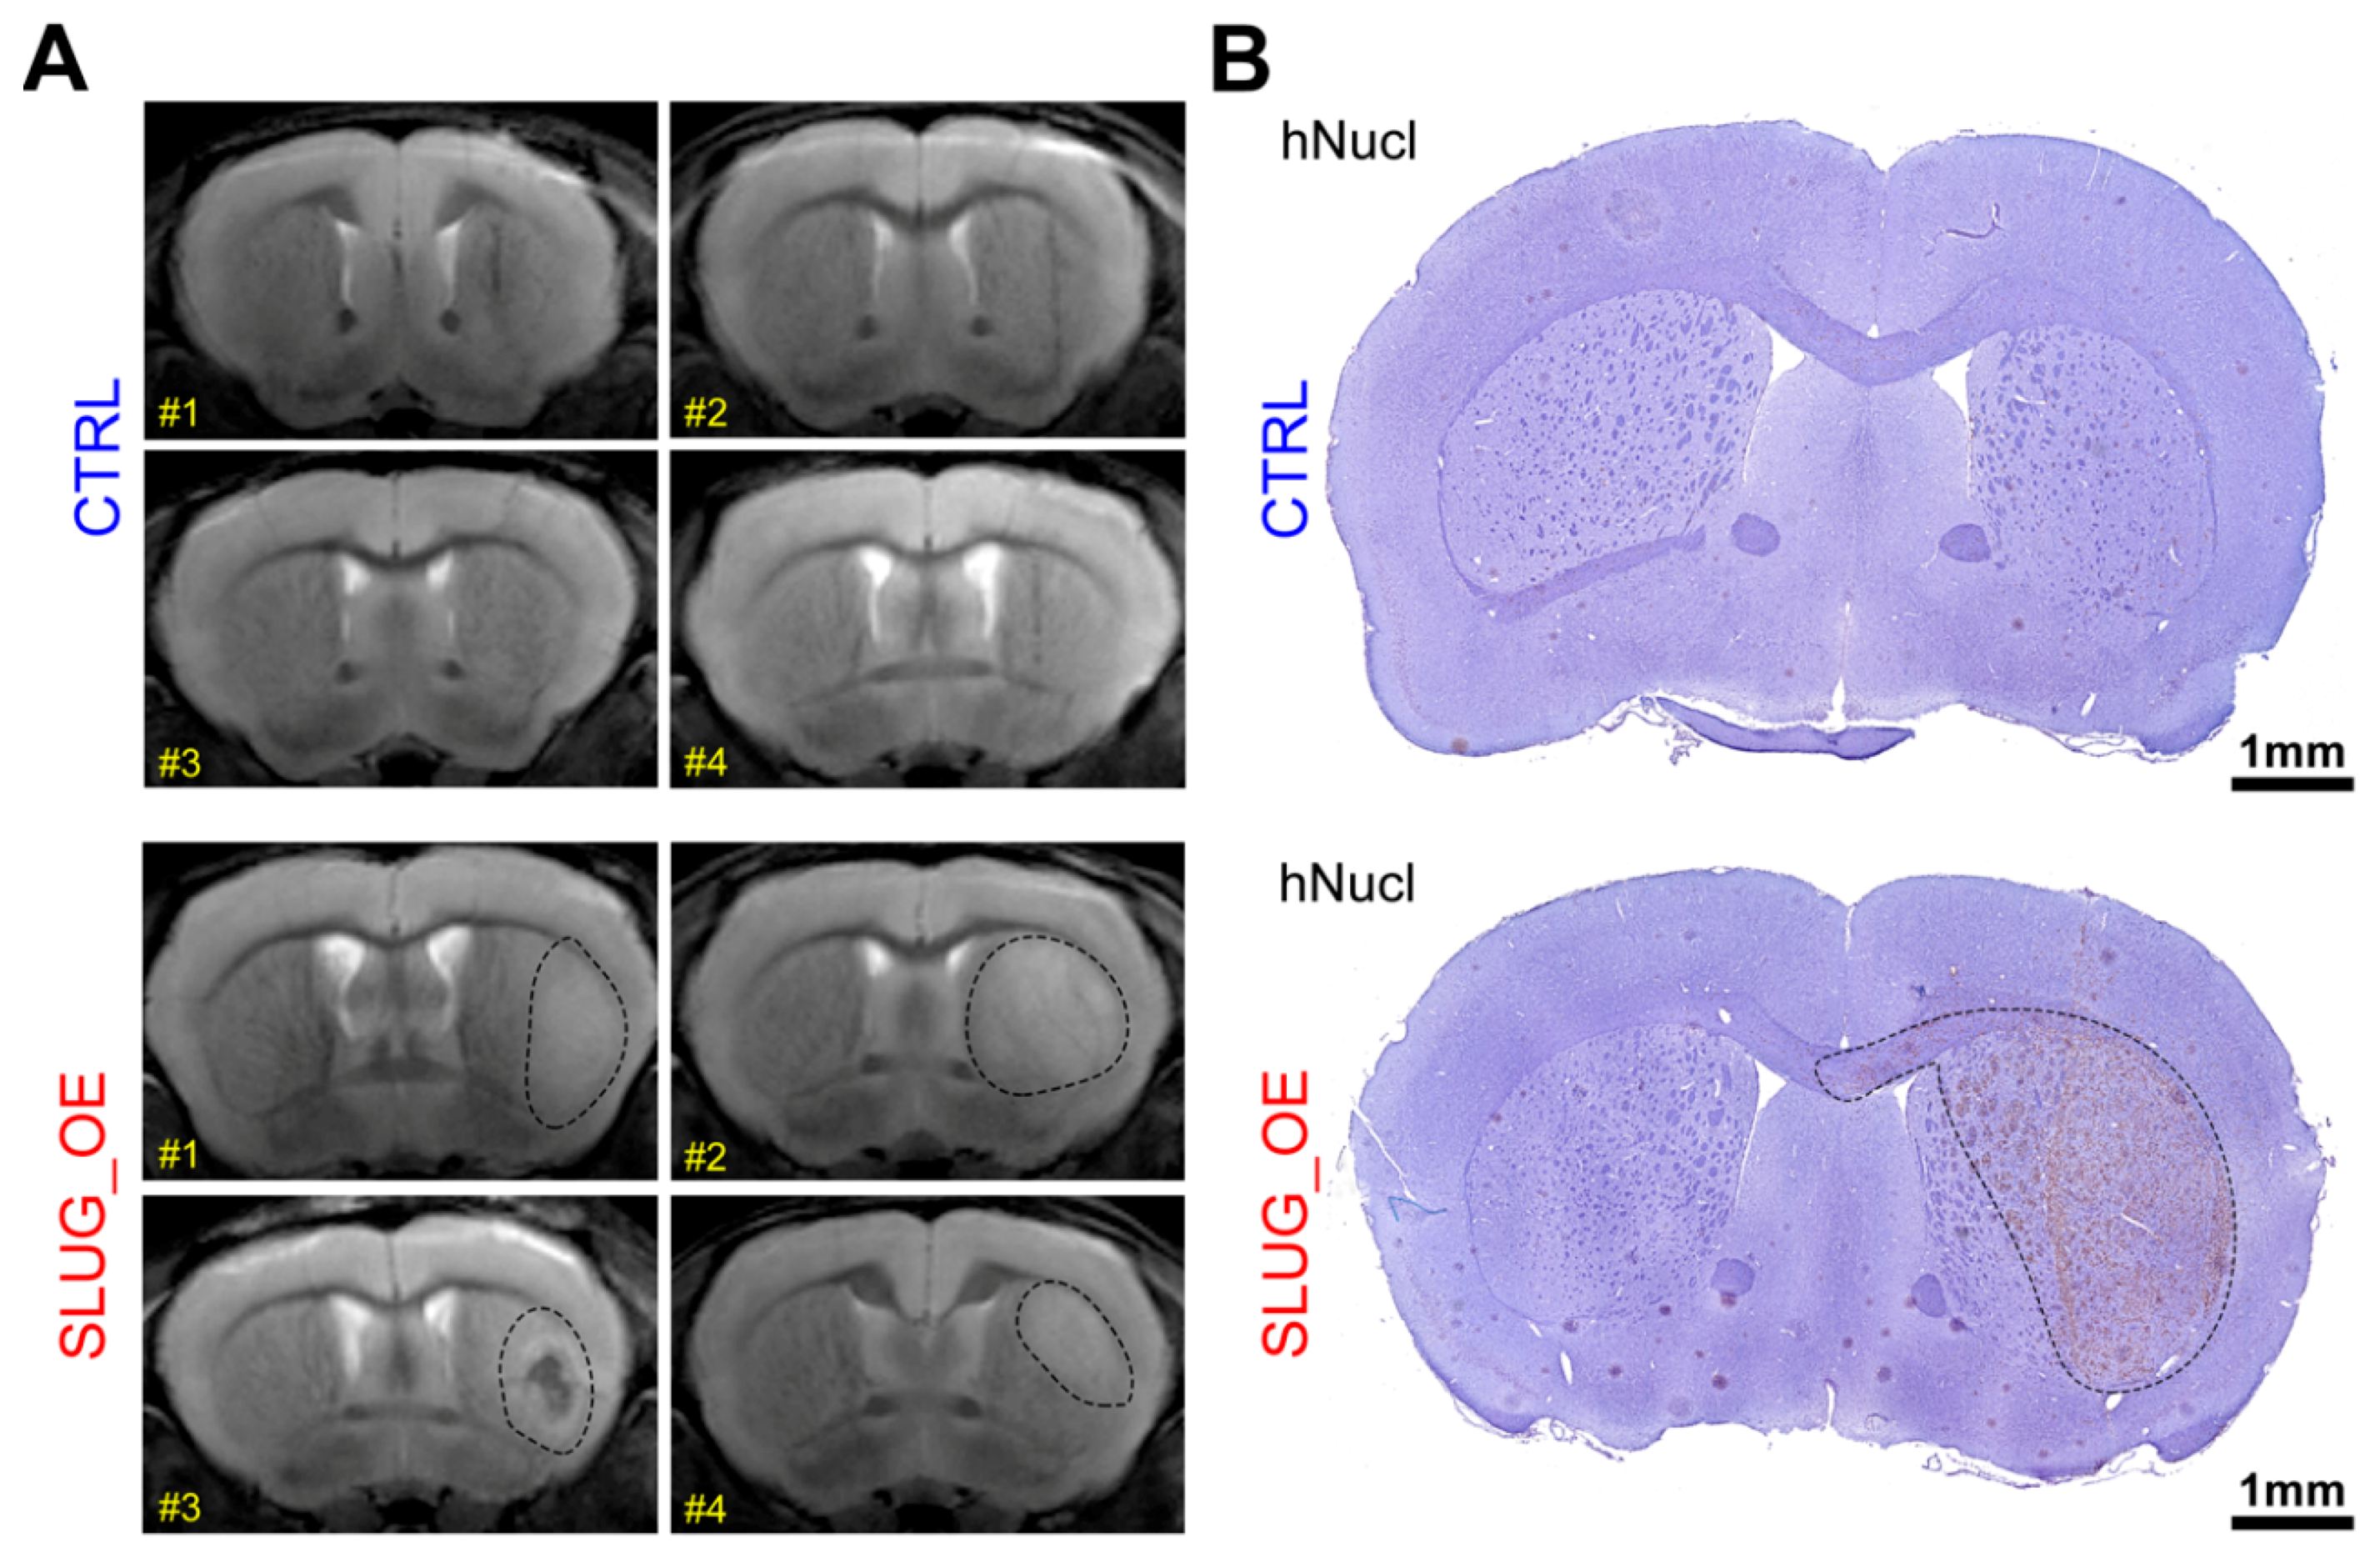

To evaluate whether SLUG promotes a transition toward a more progenitor-like precursor state, we overexpressed SLUG in one of our most stem-like BTSC lines (BT50). We then xenografted these BT50 SLUG_OE and CTRL cells in the striatum of 6- to 8-week-old female C17/SCID mice and monitored the animals by MRI. A year post-xenograft, all BT50 SLUG_OE mice started to present large enhancing regions in the xenografted hemisphere and one mouse displayed a large hematoma/necrosis-like feature (BT50 SLUG_OE mice #3). Remarkably, MRI did not reveal any particular features in the xenografted hemisphere of BT50 CTRL mice other than the needle tract that remained visible (Figure 6A). These MRI images strongly suggest development of tumors in BT50 SLUG_OE but not BT50 CTRL mice. As these mice were likely to start developing age-related symptoms unrelated to brain tumors after this one year post-xenograft time point, we elected not to perform a Kaplan Meier survival study and rather chose to focus on this earlier phase of tumor development. All of the study animals were thus sacrificed for further histological analysis. Immuno-histological hNucl staining confirmed the absence of tumors in CTRL animals and the presence of large infiltrative tumors in SLUG_OE mice (Figure 6B). While a significantly higher number of hNucl positive cells are present in the injected hemisphere of SLUG_OE animals, compared to mice implanted with CTRL cells (Figure 6C), we did not observe increased invasion toward the contralateral side (Figure 6D). Nonetheless, these results show that SLUG overexpression increased the tumorigenic potential of this extremely slow growing, quiescent stem-like BTSC line. Strikingly, as observed in BT69 SLUG_OE tumors, BT50 SLUG_OE tumors also present activated phagocytic microglia/macrophages, while ramified microglia are observed in the contralateral hemisphere and throughout the CTRL tumors (Figure 6E).

Figure 6.

SLUG overexpression in a quiescent stem-like BTSC line promotes tumor initiation in vivo (see also Figure S8). (A) Brain MRI of mice a year post-xenograft with BT50 CTRL or SLUG_OE cells (dashed lines represent approximate delimitation of enhancing regions) and (B) representative hNucl staining (dashed line represents an approximate tumor delineation). Quantitative analysis and representative close-up hNucl staining of (C) the implanted (right) hemisphere and (D) the contralateral (left) hemisphere (error bars represent SD). (E) Representative images and 2.5× close-up inserts of Iba1 staining in the xenografted and contra-lateral hemispheres of CTRL and SLUG_OE xenografted mice.

4.12. MRI

Animals were monitored in the Experimental Imaging Center (University of Calgary, Calgary, Alberta, Canada). T2 weighted sequence with cryocoil, (TE 48 ms) was performed using a 9.4-T Bruker horizontal-bore magnetic resonance (MR) system. MRI was used to detect any lesion (enhancing or not) that could potentially represent tumor growth, edema, tumors necrosis/hematomas. Dashed lines on images (Figure 6A) loosely delineates areas of abnormal enhancement that potentially represent tumor growth. MRI was strictly used to define the earlier time point at which animals should be euthanized for further histologic analysis. Interpretations as to the presence of a tumor was based solely on histology and hNucl staining.